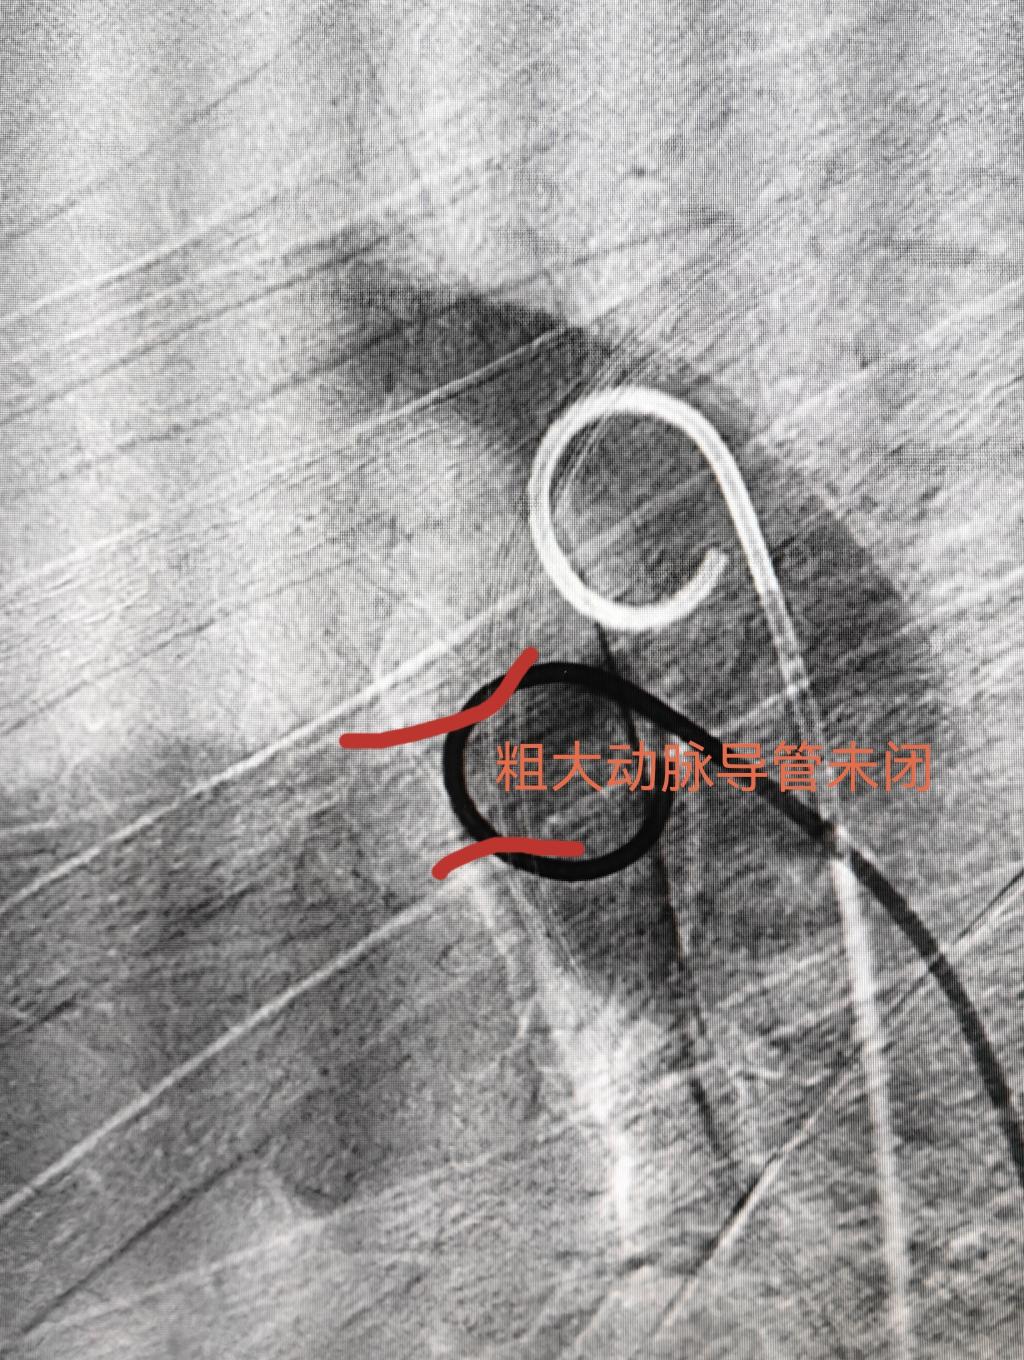

入院后第五天,完成充分的术前准备后,由相里伟医生主刀,张忆雯医生和董泽平医生协助,在导管室人员的配合下,按计划进行介入手术。血管穿刺,主动脉造影,肺动脉测压都顺利完成,也完全证实了术前影像学测量及病情判断。术中遇到的“拦路虎”是经肺动脉通过PDA困难,就改从主动脉侧超选择进入肺动脉,经股动脉送入圈套器去抓捕股静脉侧预置在腔静脉或肺动脉的导丝,期间经历了圈套器无法进入腔静脉和右心室敏感极易诱发阵发性室速等障碍,经过手术团队耐心的尝试,默契的配合和精巧的技术操作下成功建立了封堵器释放轨道。最关键的时刻到了,当封堵器沿着输送鞘缓慢送达降主动脉位置,依次释放主动脉侧封堵盘,封堵器腰部,肺动脉侧封堵盘,透视下腰征清晰,牵拉实验稳定,造影分流完全消失,听诊心前区杂音完全消失,动脉导管未闭介入封堵获得成功,意味着患者可以避免创伤大风险高的外科手术(图3、4、5)。更令人欣喜的是,当动脉导管未闭治愈的同时,左右心房间的卵圆孔未闭分流也瞬间消失了,甚至导丝尝试通过也变得很困难,再去处理卵圆孔未闭也已经失去必要性了,单纯动脉导管未闭封堵手术达到了“一石二鸟”良好疗效。